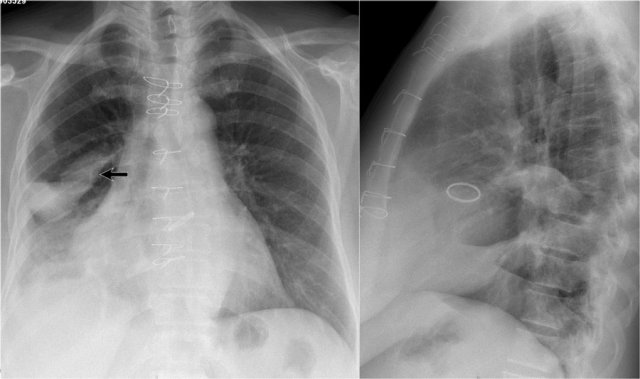

Study the CXR of a 70-year old male who fell from the stairs and has severe pain on the right flank..

Notice on the PA-film the absence of the little finger on the right and on the lateral view the increased density over the lower vertebral column.

What is your diagnosis?

There is a right lower lobe atelectasis.

Notice the abnormal right border of the heart.

The right interlobar artery is not visible, because it is not surrounded by aerated lung but by the collapsed lower lobe, which is adjacent to the right atrium.

On a follow-up chest film the atelectasis has resolved.

We assume that the atelectasis was a result of post-traumatic poor ventilation with mucus plugging.

Notice the reappearance of the right little finger (red arrow) and the normal right heart border (blue arrow).